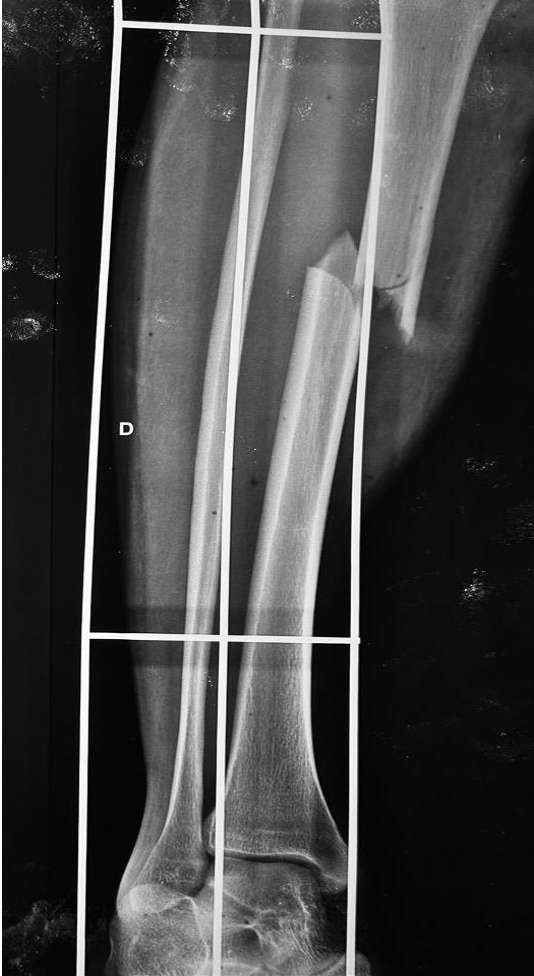

Paciente masculino de 20 anos, natural da Colômbia e residente em Porto Velho, Rondônia, sofreu uma colisão entre motocicleta e automóvel, sendo arremessado contra um muro. Na admissão, cinco horas após o acidente, radiografias revelaram luxação coxo-femoral posterior direita, luxação posterior de joelho direito (Figura 1), fratura do anel pélvico (Figura 2) e fratura diafisária da tíbia direita (Figura 3), além de lesão neurológica no membro inferior, sem comprometimento vascular.

Figura 3 – Fratura diafisária da tíbia direita

Descrição: Radiografia em AP da perna direita, com a presença de artefato (tala flexível de imobilização), realizada logo após o trauma em pronto socorro. Solução de continuidade em terço médio da tíbia direita.

Fonte: Banco de dados do Hospital de Base Dr. Ary Pinheiro – HBAP.